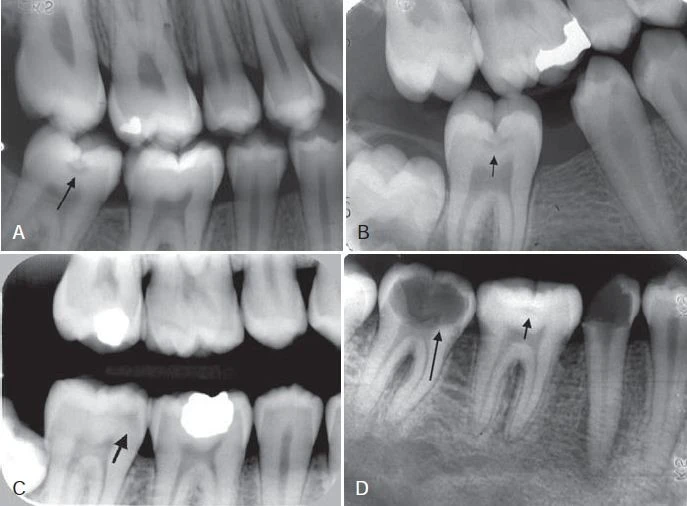

Hình 6. Phim cánh cánh thể hiện sâu răng mặt bên (mũi tên)

Hình 7. Sâu răng lan rộng vào phần ngà răng

Hình 8. Mặt tiếp xúc bên là vùng dễ bị sâu răng, vùng này đi từ điểm tiếp xúc đến bờ nướu tự do.

Hình 9. Sâu răng ở răng cạnh răng mang miếng trám do quá trình tạo xoang trám làm tổn thương bề mặt răng kế cân.

Thậm chí những nha sĩ nhiều kinh nghiệm cũng thường không đồng ý với việc có hay không có sâu răng khi kiểm tra trên một lần chụp X quang khi tổn thương chỉ giới hạn ở phần men răng. Đôi khi có thể phát hiện sai tổn thương sâu răng khi bề mặt răng không bị ảnh hưởng (kết quả dương tính giả). Nhiều hiện tượng hình thái chẳng hạn như những trũng và rãnh, chỗ lõm vùng cổ răng, hiệu ứng dải Mach, những bất thường về răng chẳng hạn như những rãnh giảm sản và những chỗ lõm do mòn răng cũng có thể giả dạng hình ảnh sâu răng. Trong những trường hợp mất khoáng không biểu hiện rõ trên X quang, việc không phát hiện được thương tổn được gọi là kết quả dương tính giả. Ngoài ra, những điểm tiếp xúc chồng lên nhau trên hình ảnh X quang có thể che lấp mất tổn thương. Khoảng một nửa tất cả những tổn thương mặt bên ở phần men răng không thể phát hiện được trên X quang.

Hình 10. Những hình ảnh dương tính giả (mũi tên)